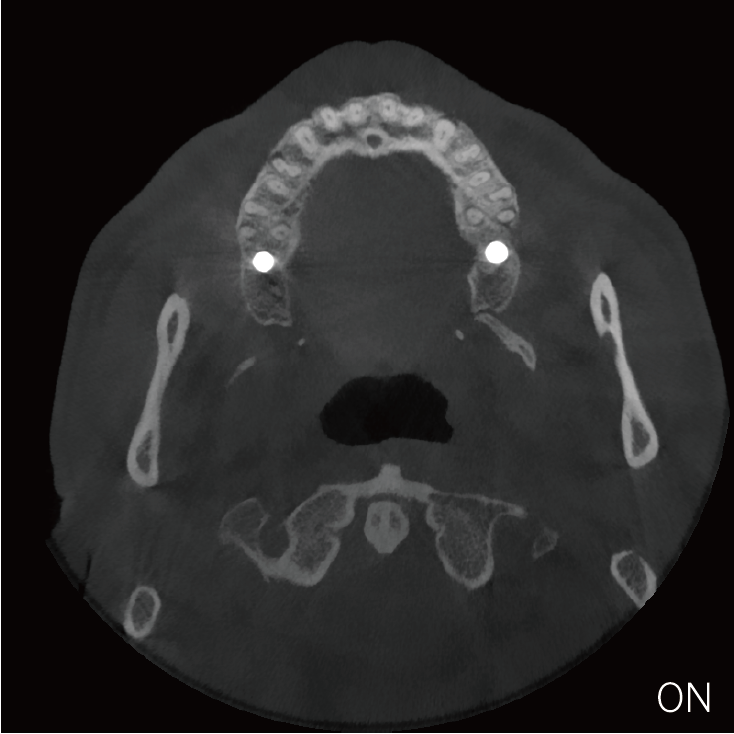

超能去伪 至臻影像

临床样片